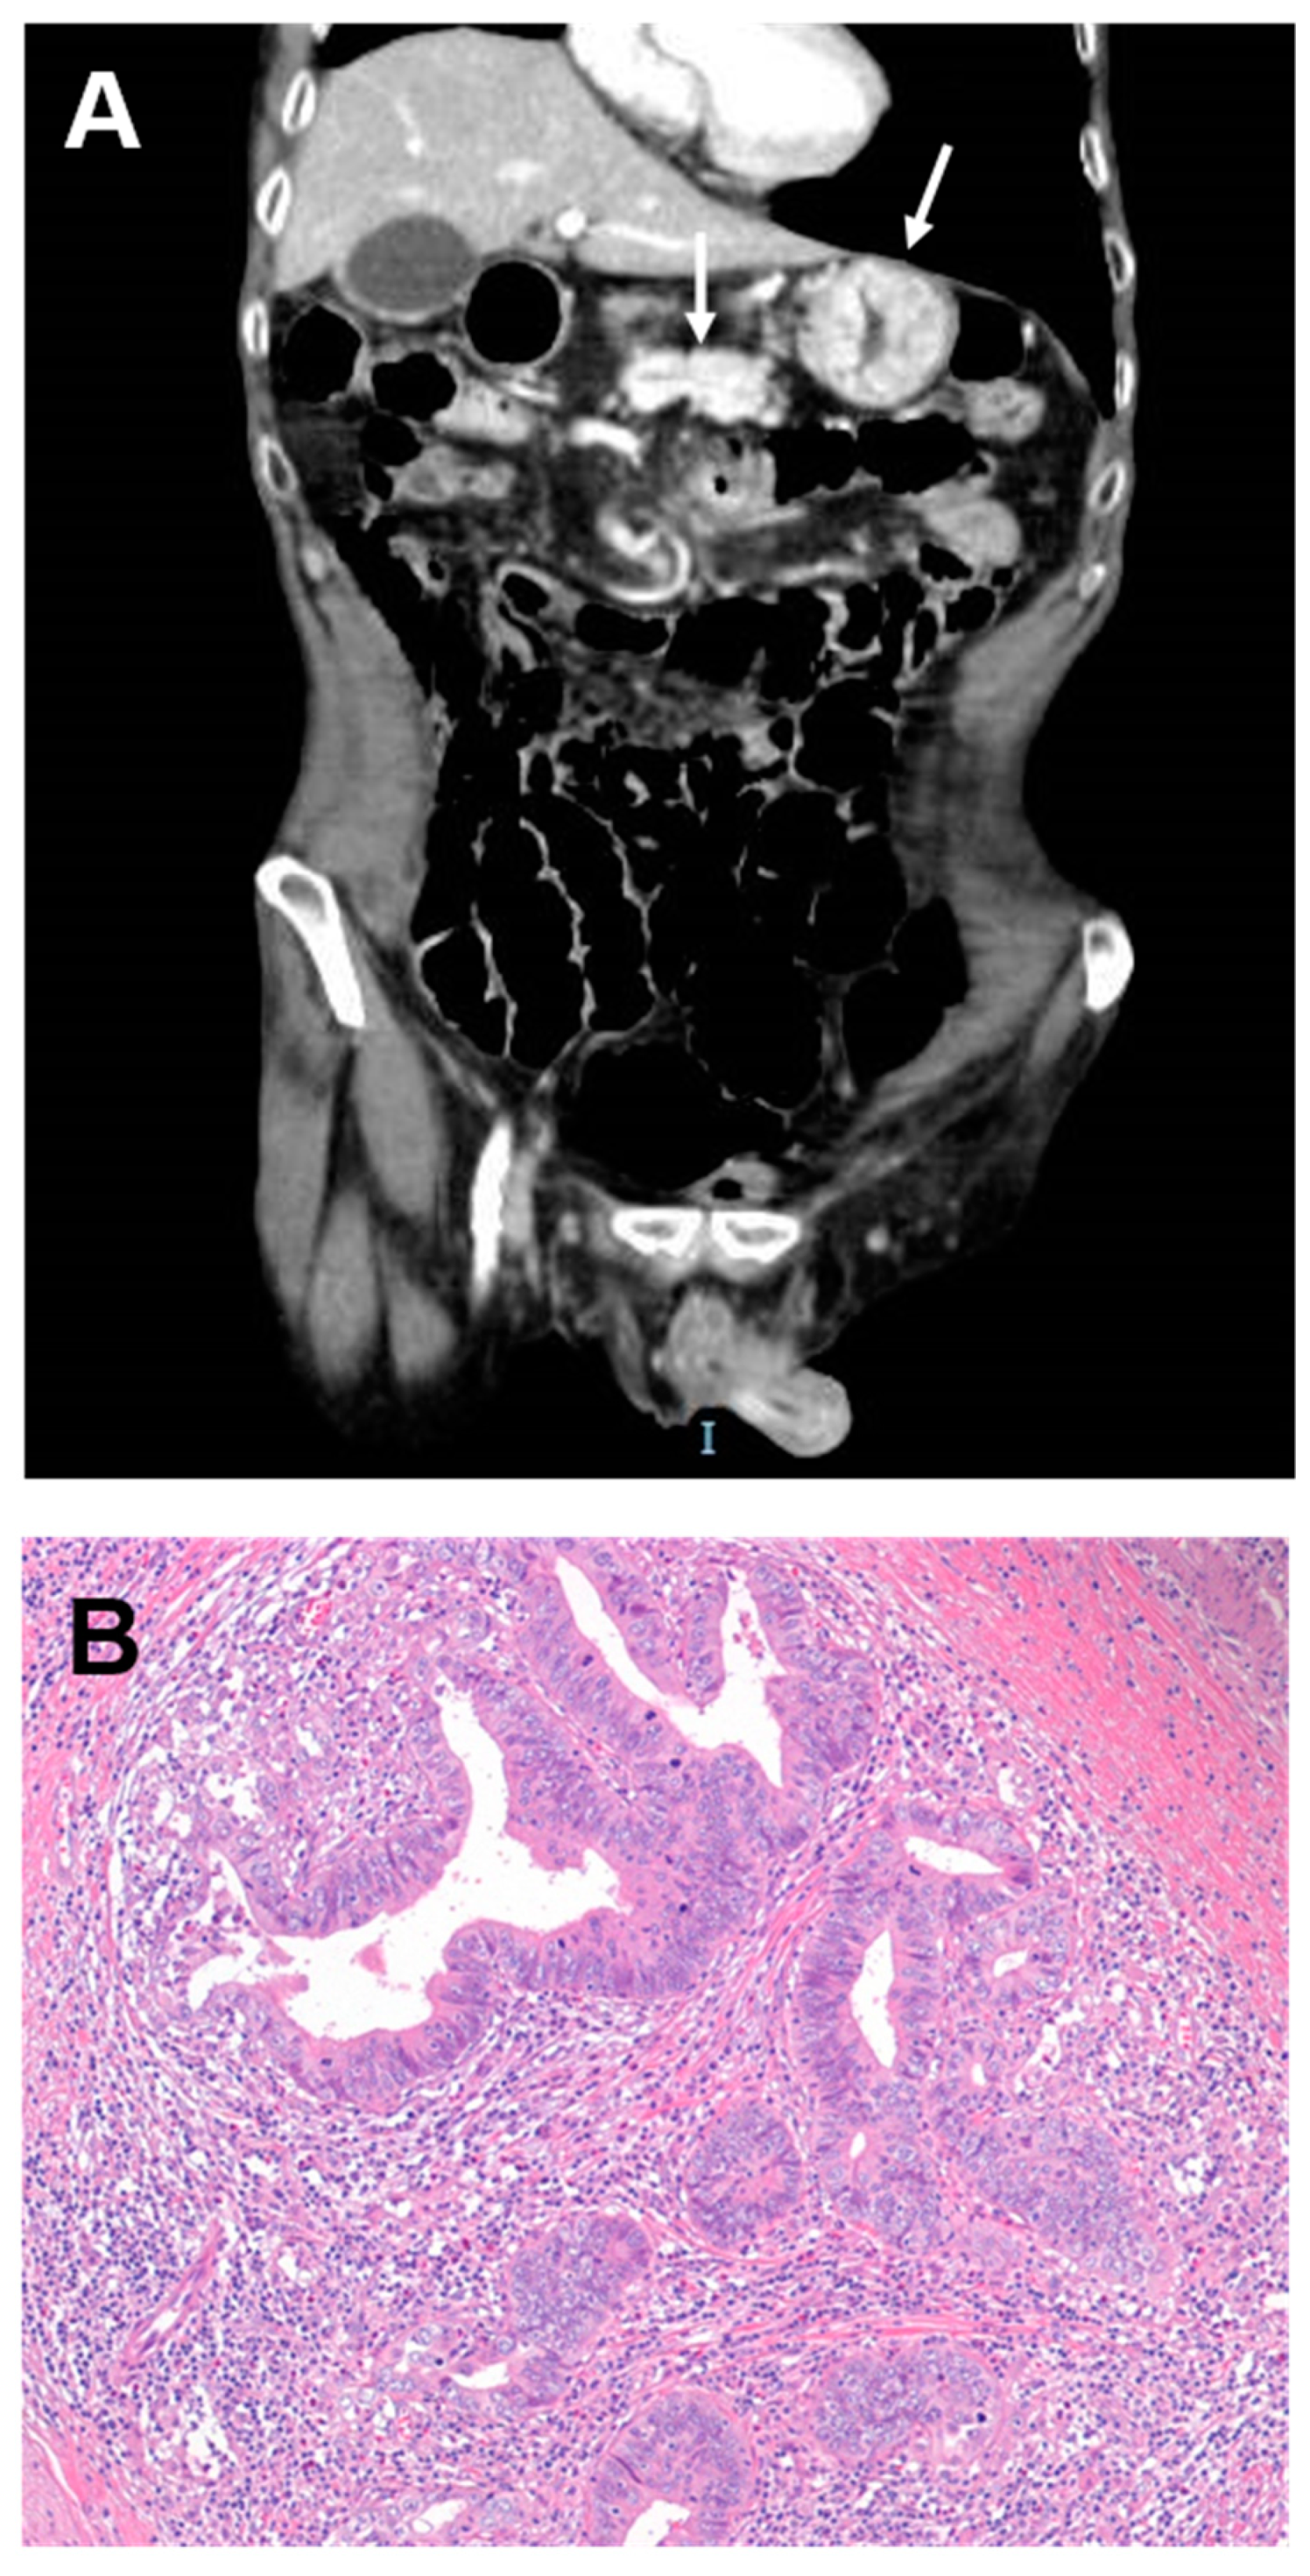

Figure 2.

(A,B) Radiologic and histologic images of a coeliac disease-associated small bowel carcinoma. (A) Computed tomography shows a circumferential mass with shouldered borders causing the wall thickening in the duodenum (arrows). (B) Haematoxylin and eosin staining shows a glandular-type carcinoma with a high tumour-infiltrating lymphocyte density. Original magnification: 100×.